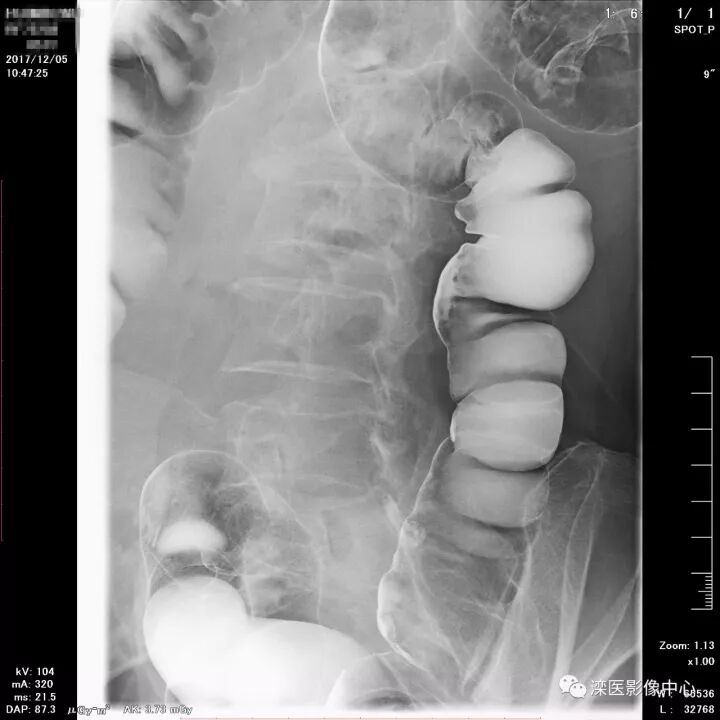

下面请您审阅近期我院影像科开展下消化道双对比造影检查的图像:

(俯卧位观察直肠、乙状结肠及降结肠)